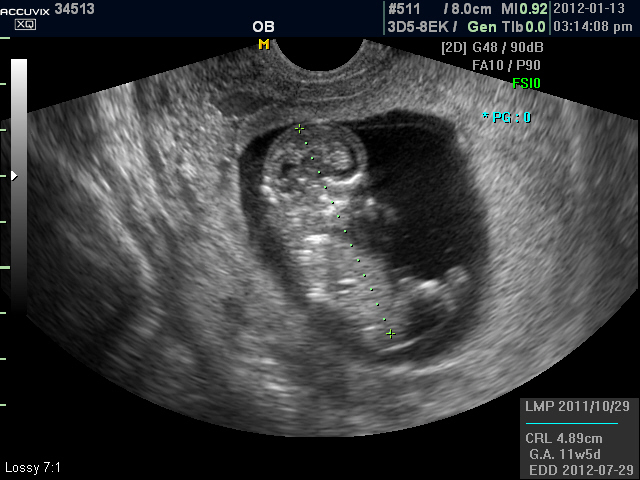

위 사진은 본원에서 찍은 임신 초음파로 12주 된 태아의 2차원 이미지와 입체 모습입니다.